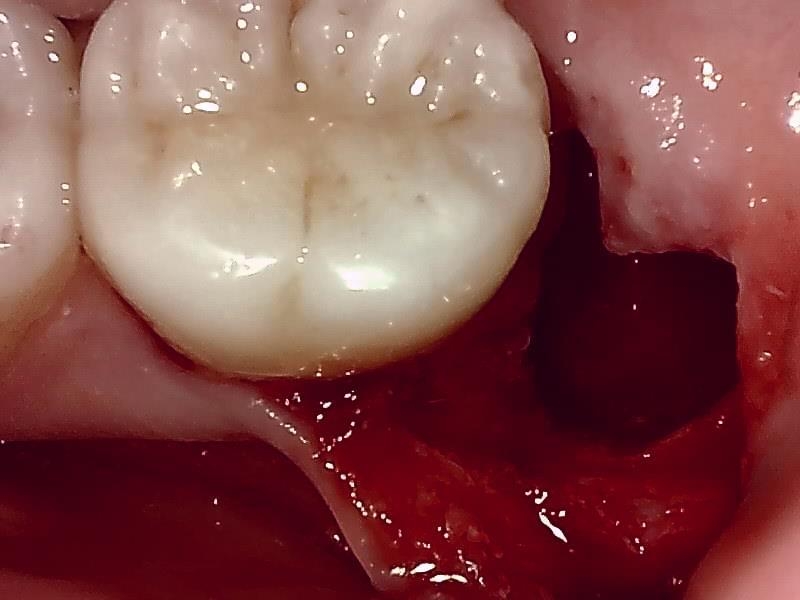

抜歯窩

縫合

術後

治癒

この抜歯法により術後の腫れ痛みが大幅に軽減されます。

抜歯後、経過良好です。